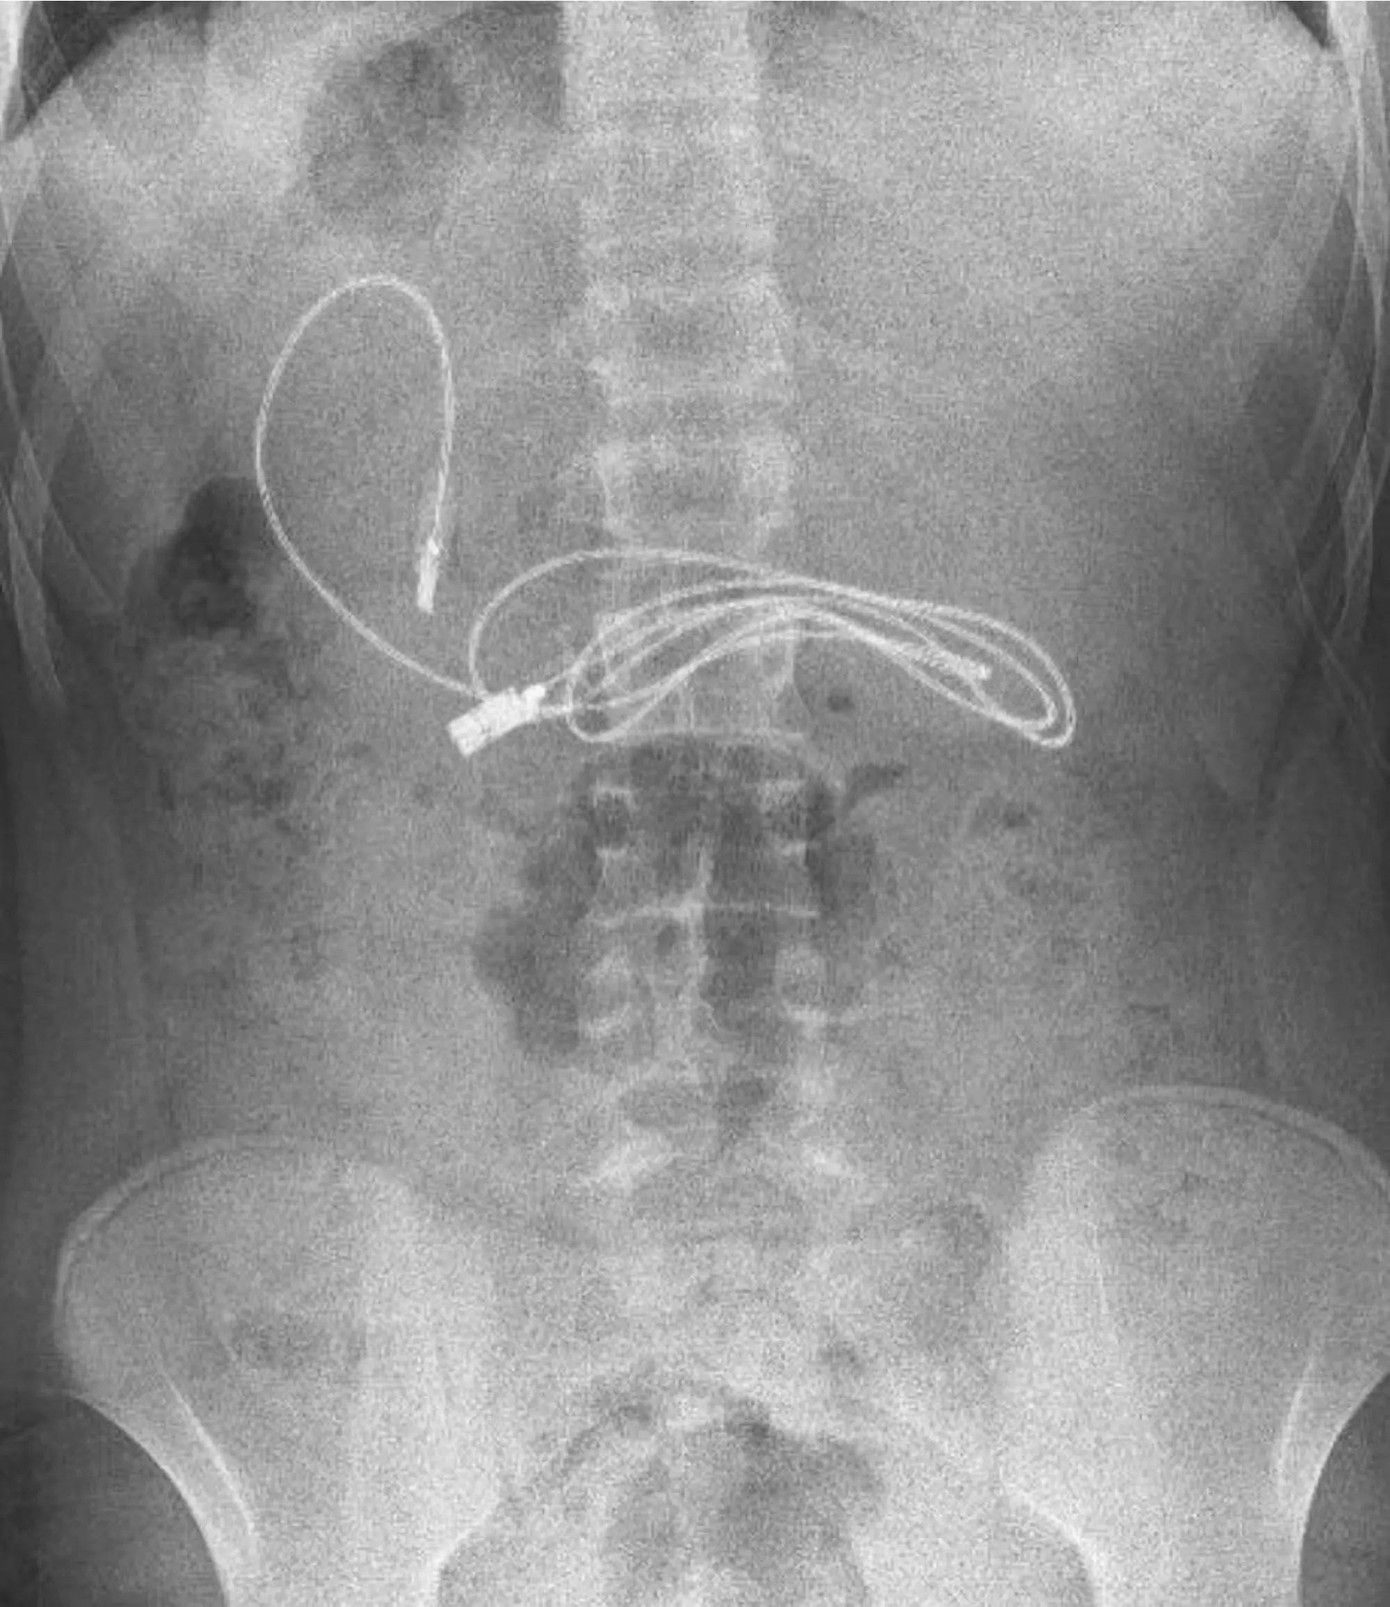

| Hình ảnh chụp X-quang thấy rõ dị vật trong người cậu bé 15 tuổi |

Cậu bé đến từ Diyarbakir, Thổ Nhĩ Kỳ, được gia đình vội vàng đưa đến bệnh viện sau khi kêu buồn nôn và đau bụng. Chụp X-quang nhanh chóng tiết lộ ra rằng, dây bọc nhựa đang chờ tiêu hóa trong dạ dày cậu bé.